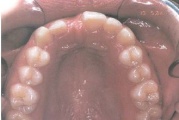

Ülemise hambakaare kitsenemine ehk tagumiste hammaste risthambumus.

alumine hambakaar on laiem ülemisest

ülemine hambakaar on alumisest laiem nõnda palju, et hambad kokku ei puutu